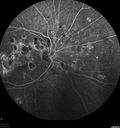

FLUORESCEIN ANGIOGRAPHY: Fluorescein angiography of the right eye shows multiple hyperfluorescence spots in the macula where the scarring is. The left eye shows an increasing hyperfluorescencent area under the fovea, which does look to be vascular, likely from a neovascular complex.

Punctate Inner Choroidopathy - Recurrent CNVM 4 years after initial treatment Left Eye - Fluorescein Angiogram647 viewsJune 7, 2012. This pleasant 35-year-old woman noticed decreasing vision in the left eye recently. She returns now noticing the vision in the left eye is declining. OD 20/50, OS 20/80. OS: Vertical C/D ratio is 0.3. There is a scar just inferonasal to the fovea, which has grown some towards the fovea with a little blood just under the fovea.

(0 votes)